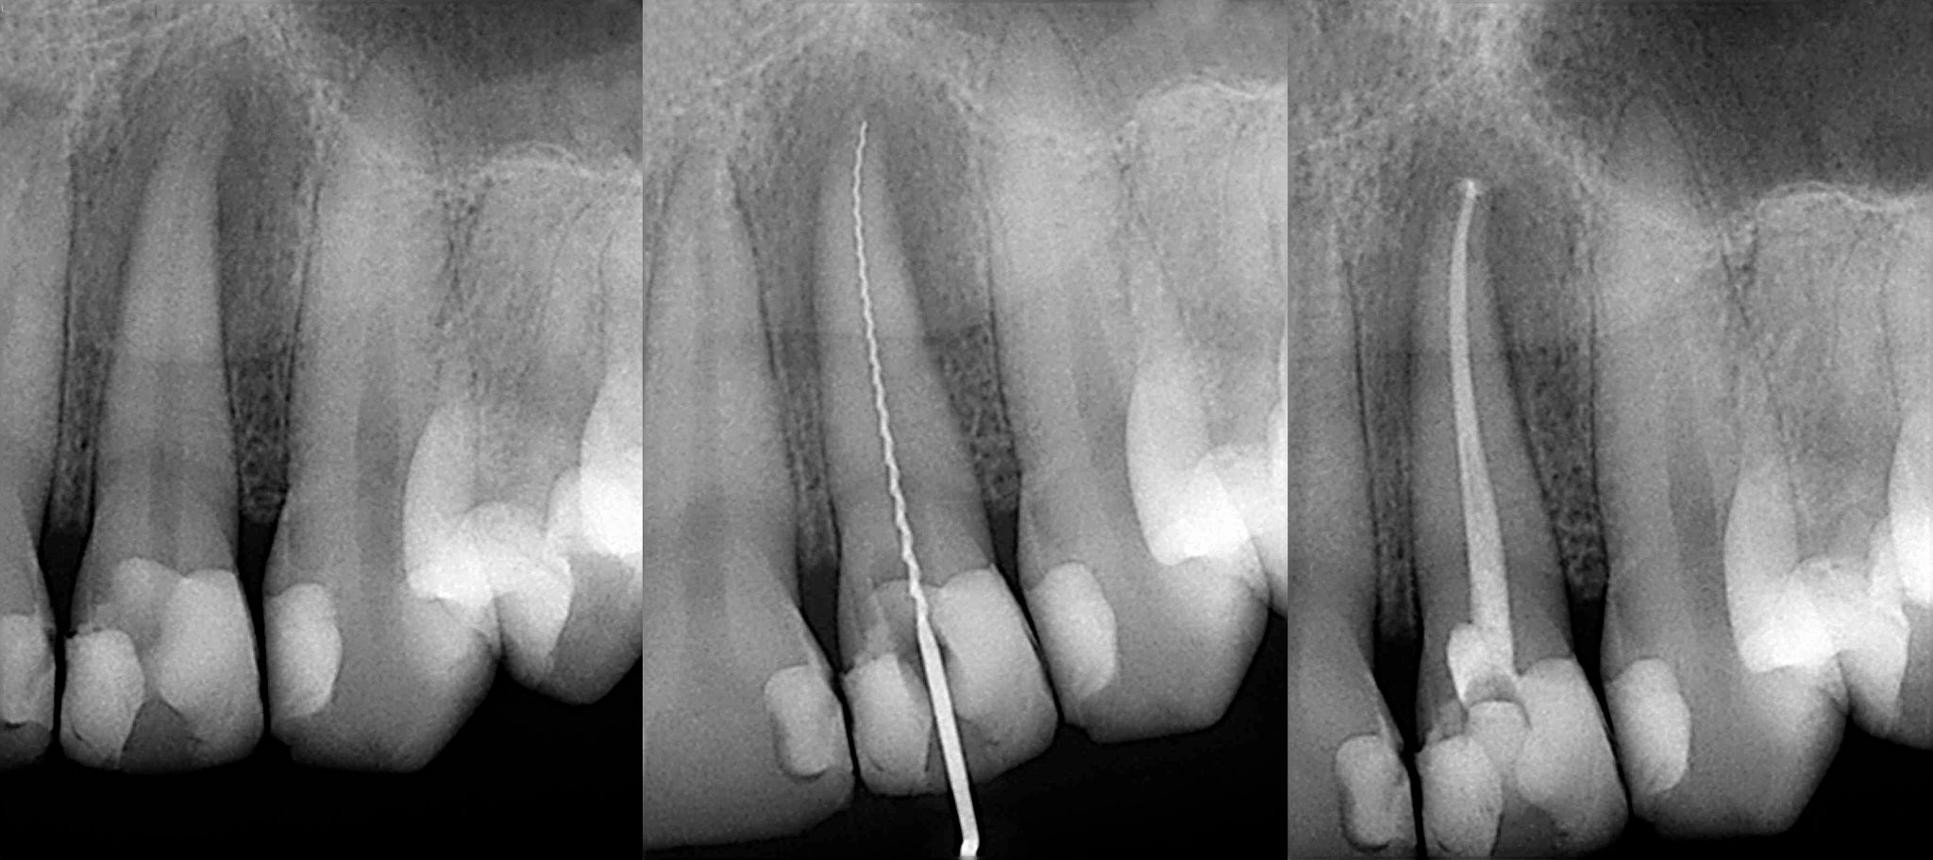

4. Dental X-Rays (Most Important Step)

X-rays play a crucial role in diagnosing the need for RCT treatment. They help dentists see:

• Infection at the root tip

• Bone loss around the tooth

• Deep cavities reaching the pulp

If the infection is visible on an X-ray, root canal treatment in Bangalore is usually necessary.